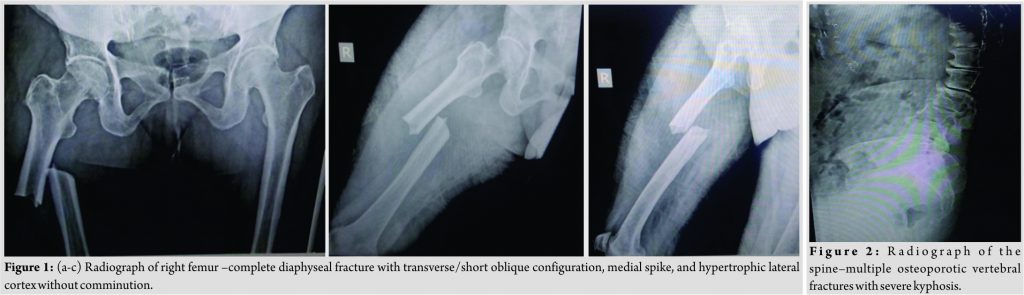

A 73-year-old lady with no history of previous trauma presented to our trauma center with a history of sudden onset pain over the right thigh after a jerk while getting up from a chair. The patient gave the history of seropositive rheumatoid arthritis and osteoporosis with compression fractures of vertebrae for which she was on disease-modulating antirheumatoid drugs and bisphosphonate (Anti-resorptive) medications. The patient also received a dose of denosumab 60 mg subcutaneously 2 weeks before the incident. On admission, the radiographic examination of right femur showed complete fracture at the diaphyseal level of transverse/short oblique configuration without comminution with a medial spike and concomitant hypertrophic lateral cortex (Fig. 1a, b, c). Radiograph of the spine showed multiple osteoporotic vertebral fractures with severe kyphosis (Fig. 2).